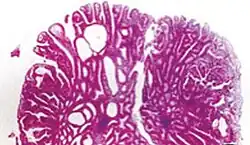

| Tubular adenoma | 2% at 1.5 cm[12] | Low to high grade dysplasia[13] | Over 75% of volume has tubular appearance.[14] |

The common adenomas of the colon (colorectal adenoma) are the tubular, tubulovillous, villous, and sessile serrated (SSA).[18] A large majority (65–80%) are of the benign tubular type with 10–25% being tubulovillous, and villous being the most rare at 5–10%.[9]

- Tubular adenoma: 5% risk of cancer

Micrograph of a tubular adenoma, the most common type of dysplastic polyp in the colon -

Micrograph of a tubular adenoma – dysplastic epithelium (dark purple) on left of image; normal epithelium (blue) on right. H&E stain. -